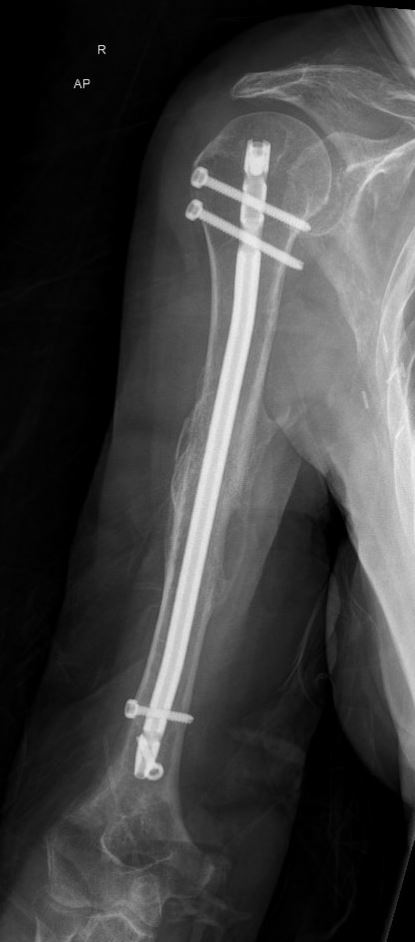

Indien u geopereerd wordt, zal de traumachirurg proberen de breukdelen van de schacht weer in de juiste vorm en richting aan elkaar te zetten. Hiervoor heeft uw traumachirurg verschillende opties, afhankelijk van het type breuk en de voorkeur van uw chirurg. Veel gebruikt is een pen in de mergholte van het bot, die via de schouder of via de elleboog kan worden ingebracht. De pen wordt vervolgens met dwarse schroefjes aan het begin en het einde van de pen vastgezet. Een andere optie is het gebruik van platen en schroeven om de verschillende breukdelen stevig aan elkaar vast te zetten. Voor het plaatsen van een plaat is wel een grotere snede nodig dan voor een pen. Welke operatie u uiteindelijk krijgt, is afhankelijk van de eigenschappen van de breuk, uw eigen toestand en de voorkeur van de chirurg.

Meestal zult u na de operatie een mitella of draagband krijgen, zodat de arm rust kan krijgen. Hoe lang u na de operatie rust moet houden, is afhankelijk van het soort breuk en hoe stevig de chirurg de breukdelen weer aan elkaar heeft kunnen zetten. Meestal zal het zo zijn dat u tot 6 weken na de operatie uw arm niet teveel mag belasten maar al wel snel na de operatie mag gaan oefenen om het schoudergewricht en de elleboog soepel te houden.